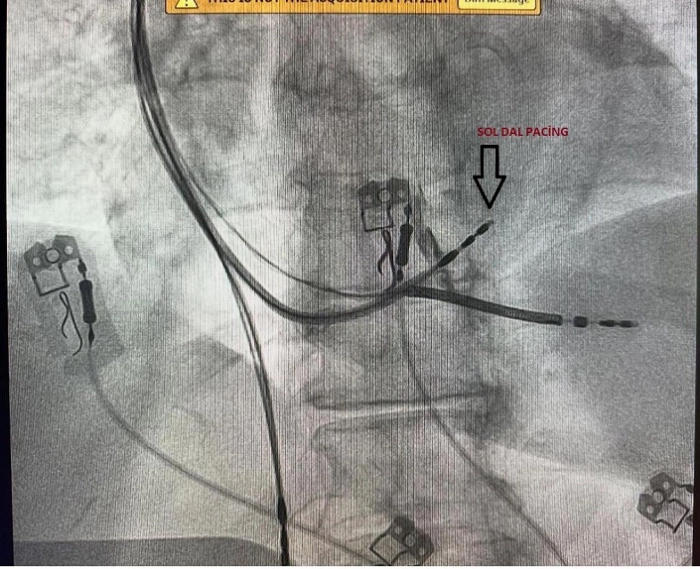

Türkiye'de sadece belirli merkezlerde yapılan ‘Sol Dal Pacing' ameliyatı Fethi Sekin Şehir Hastanesi'nde 3 hastanın ameliyat edilmesiyle başladı. Hastanede görevli Kardiyoloji Uzmanları Dr. Öğretim Üyesi Zeki Çetinkaya ve Uzm. Dr. Mehmet Ali Gelen, aldıkları eğitimin ardından hastanede ‘Sol Dal Pacing' yöntemi ile kapalı pil ameliyatını başarılı bir şekilde gerçekleştirdi. Kalbin içerisindeki çarpıntıların tespit edilmesi ve ardından ablasyon ile teknik tedavi uygulanan ameliyat yöntemi, daha önceden yapılan kalp ameliyatlarının nefes darlığı ve kalp yetmezliği oluşturmasını ortadan kaldırıyor. Başarılı ameliyatların ardından bilgiler veren doktorlar, dünyada yeni uygulanan Türkiye'de ise belirli merkezlerde yapılan ameliyat yöntemi ile Fethi Sekin Şehir Hastanesi'nin bu alanda öncü olacağını belirtti.

Türkiye'de belirli merkezlerde yapılan fakat Elazığ'da bir ilki gerçekleştirdiklerini aktaran Dr. Öğretim Üyesi Zeki Çetinkaya, “Sol Dal Pacing yöntemi ile 3 hastamızı ameliyat ettik.

Bundan sonra da bu şekilde devam edeceğiz. Bu ameliyatın özelliği kalbin doğal ileti sistemi üzerine pil kablosunu yerleştirdikten sonra kalbin sağ ve sol karıncıklarının uyumlu şekilde çalışmasını sağlıyoruz. Diğer normal taktığımız pillerde ise öncelikle kalbin sağ karıncık kısmı uyarılıyor, sonra sol karıncık kısmı geç uyarılıyordu. Bu şekilde 10 hastanın 2'sinde kalp yetmezliği ve nefes darlığı olabiliyordu. Bu pil yöntemi, dünyada yeni uygulanıyor. Hastalarımız bu ameliyat yöntemi ile daha fayda görmektedir. Özellikle ritim bozukluğu ve nefes darlığı olan hastalarda bu işlemleri başarılı şekilde uygulamaktayız. Bu ameliyat, Ankara, İstanbul ve belirli merkezlerde yapılmaktadır. Burada ise ilk defa yaptık ve başarılı olduk. Katkılarından dolayı Prof. Dr. Uğur Canpolat hocamıza da teşekkür ederiz. Buranın ilerleyen dönemlerde bölge merkezi olma ihtimali de çok yüksek. Bu ameliyatın özelliği doğal ileti sistemi üzerine kablo koyularak kalbin senkron şeklinde yani iki ventürkülün de aynı anda kasılmasını sağlıyoruz. Bu şekilde hastalarda nefes darlığı daha az oluyor. Bu pil yöntemi takıldığında hastalarımız daha konforlu ve nefes darlığı olmayacak şekilde yaşamlarını devam ettirebilirler” dedi.